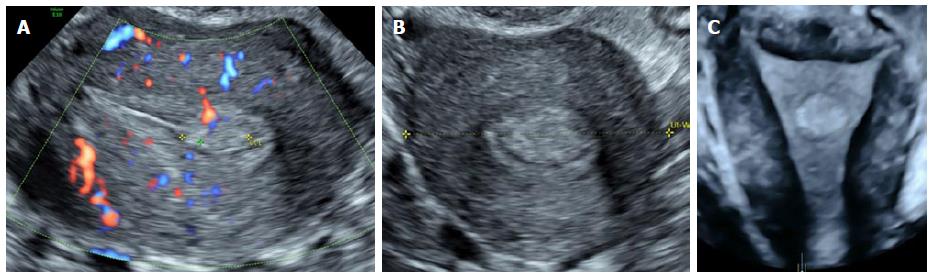

Медицинская диагностика: Гиперплазия эндометрия на УЗИ